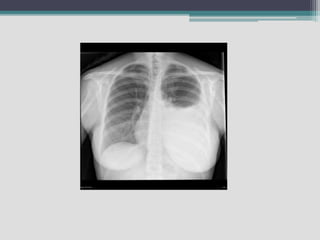

Emphysema

• Emphysema occurs when some of the air sacs

deep in the lungs are damaged, often because

of long-term infection and irritation. When lung

tissue is damaged, the airways collapse,

trapping stale air and blocking intake of fresh air.

• The lungs try to take in more air and become

over-inflated and stretched out, gradually getting

so big they completely fill the chest cavity.

• Many with severe emphysema develop a barrel

shaped chest because of this.